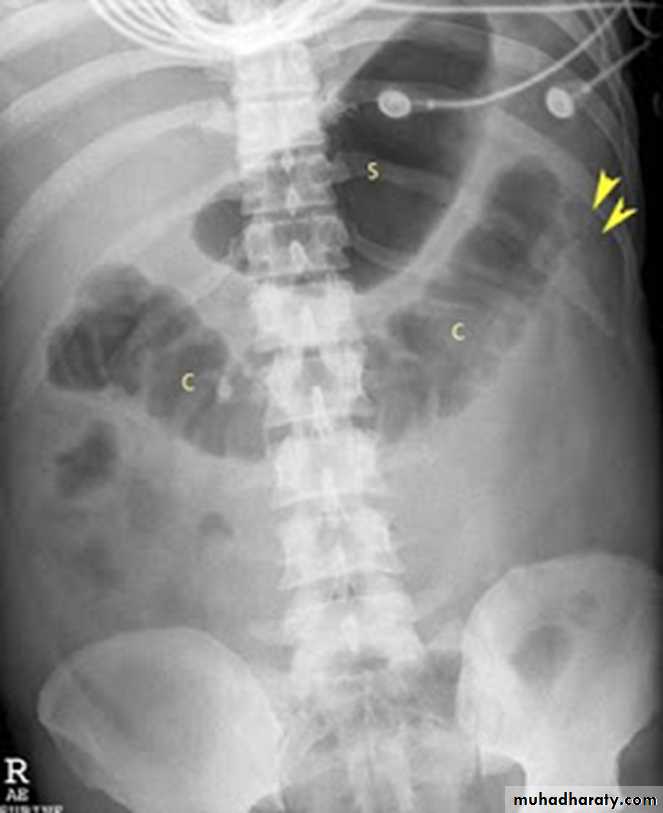

SENTINEL LOOP SIGN

COLON CUT-OFF SIGN